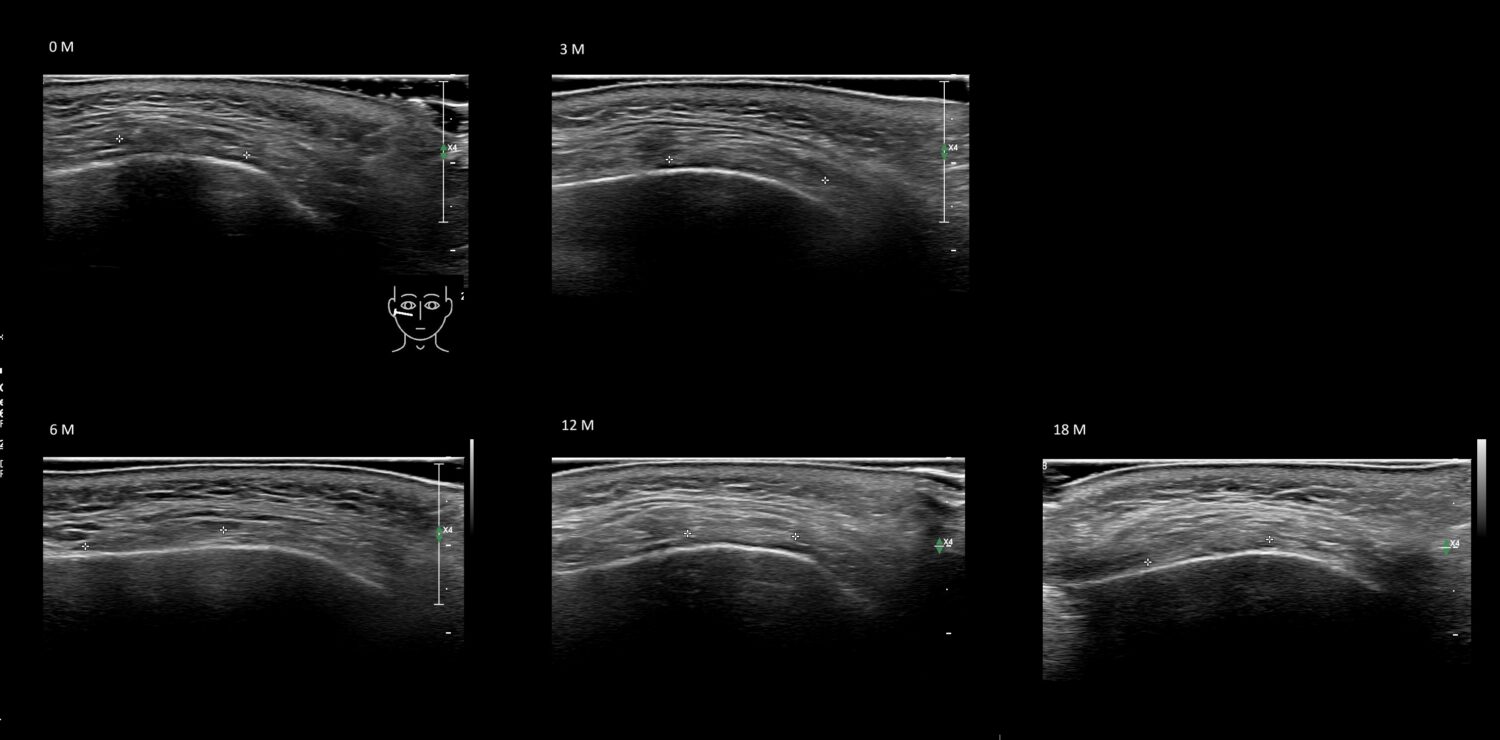

Filler library